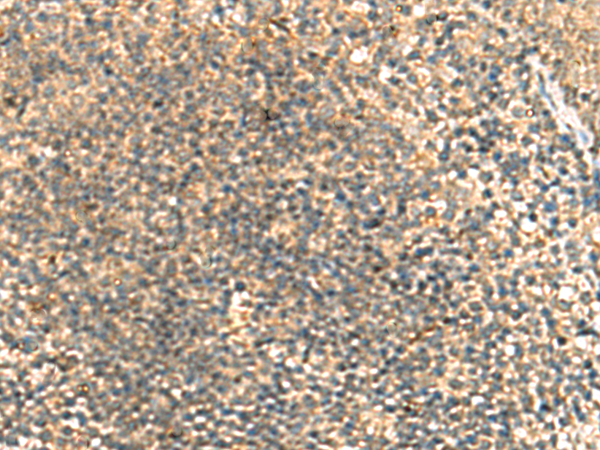

IHC positive control: |

Human tonsil and Human thyroid cancer |